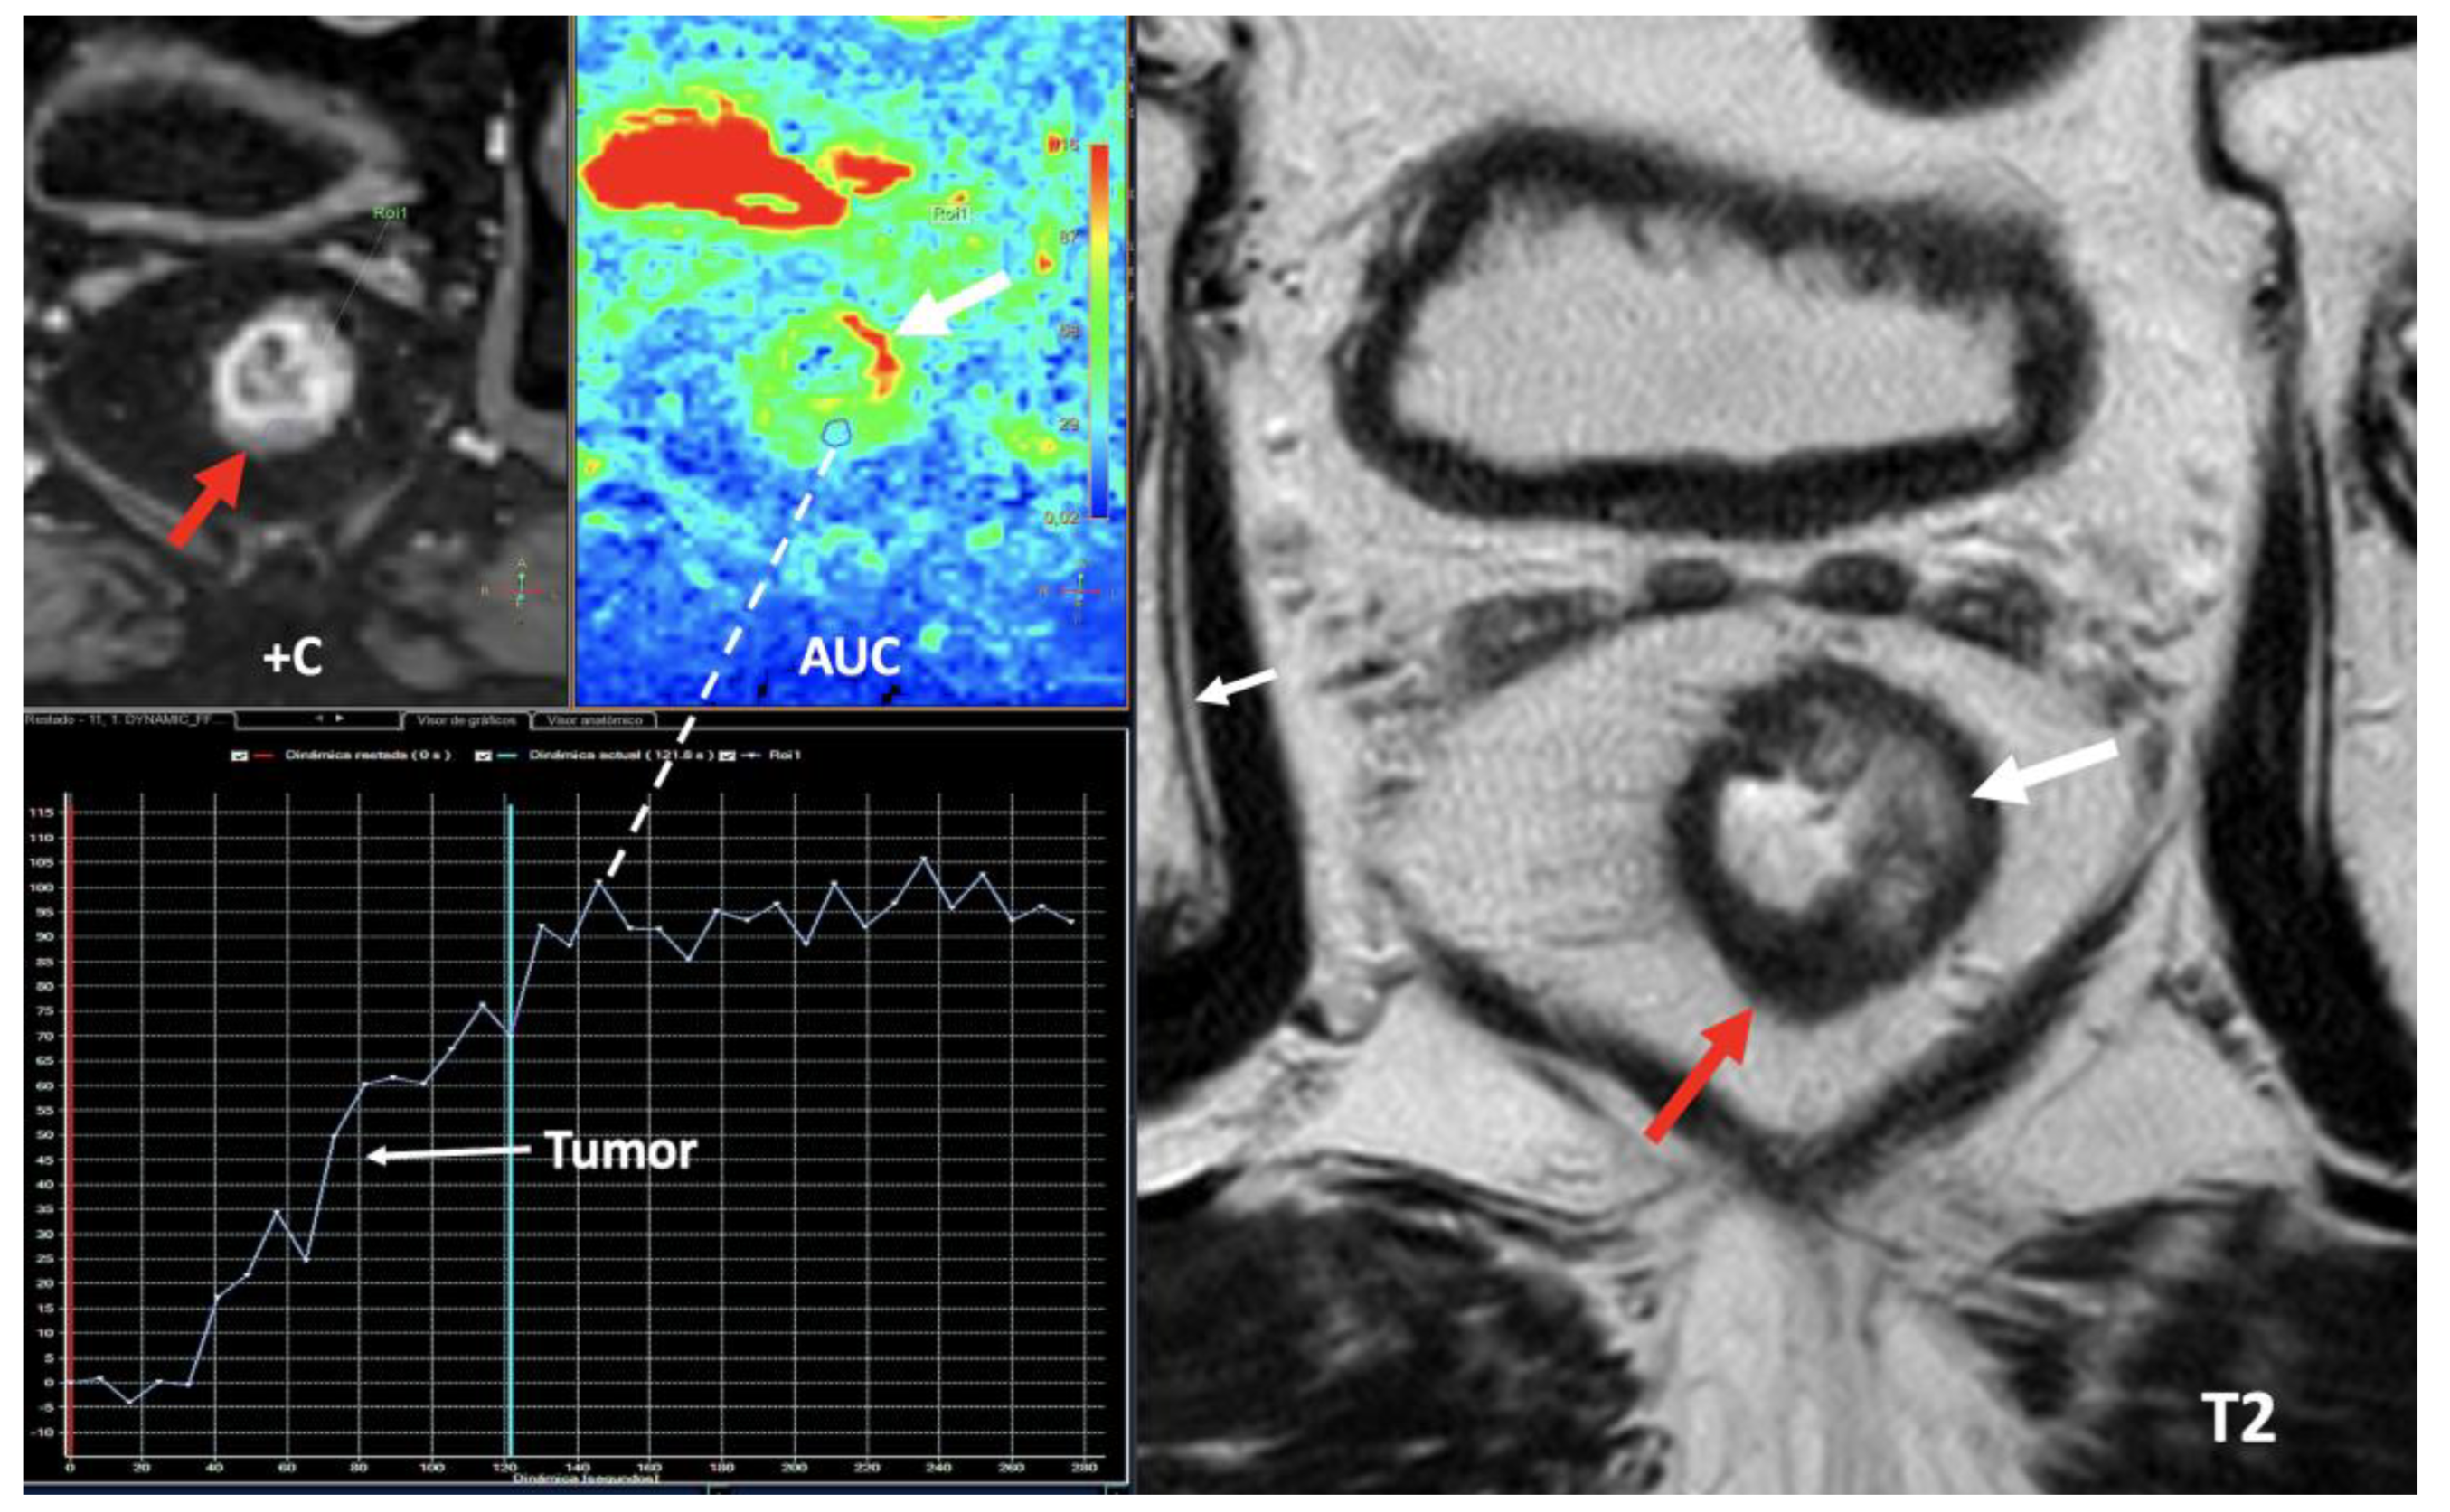

- Currently, there is not a widely reported use of DECT in clinical management of prostate cancer. However, DECT imaging may facilitate the depiction of focal areas of increased enhancement in the periphery of the prostate at contrast-enhanced CT that may represent a clinically significant cancer and deserve further workup [42] [Figure 13].